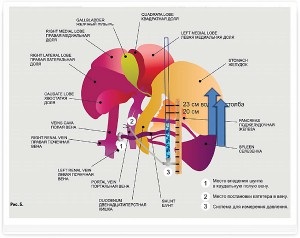

Porto (portocav) șunturi - este conexiuni vasculare anormale între vena portal hepatic (vas de sânge care se conectează tractul gastrointestinal la nivelul ficatului) și circulația sistemică (Figura 2, 2a).

Figura 2 și 2a. Schemele fluxului sanguin portal patologic

Schema de măsurare a presiunii portale la câini. Când presiunea crește peste 20 cm de apă se va dezvolta ascita.